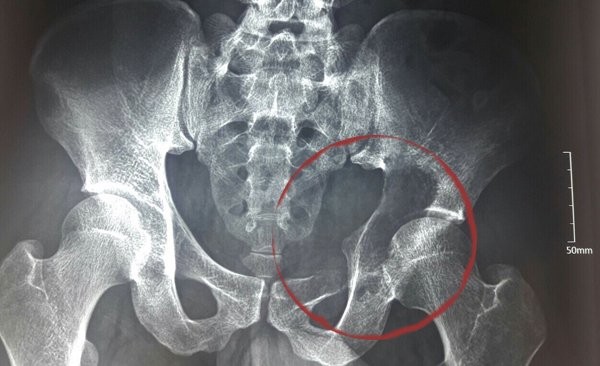

Sau khám, các bác sĩ BV K định có một khối u ở vùng ổ cối xương chậu, phá huỷ hoàn toàn ổ cối và phát triển vào ổ bụng bệnh nhân với kích cỡ khoảng 10cm, là u tế bào khổng lồ.

Các bác sĩ đánh giá, đây là ca bệnh hết sức phức tạp, vị trí khối u là nơi tập trung dây thần kinh ngồi cùng với các bó mạch thần kinh mông trên và mông dưới đi qua, là khu vực hiểm yếu, có nguy cơ tai biến trong phẫu thuật rất cao.

Ngoài ra, vùng đáy ổ cối bị phá huỷ khiến khớp háng bệnh nhân mất chức năng gần như hoàn toàn.